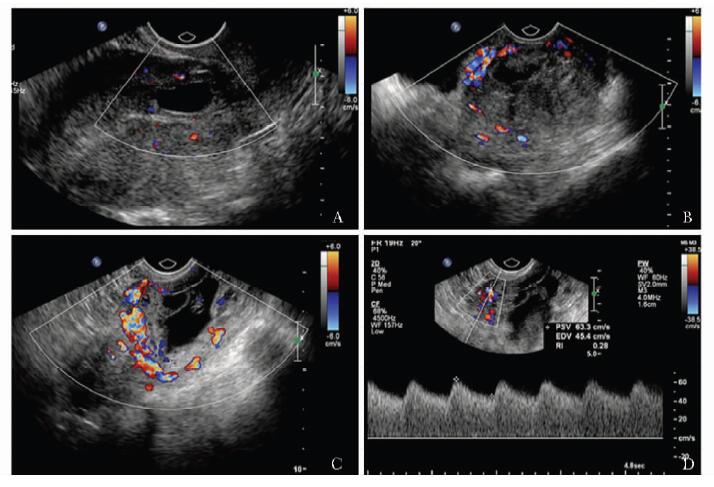

方法  收集2011年11月至2013年1月北京协和医院临床确诊为剖宫产切口瘢痕妊娠、并接受手术治疗的35例患者, 术前进行二维及三维超声检查, 获得病灶最大径、病灶平均径、病灶植入瘢痕面积、植入体积及植入深度; 按有无胎心搏动、病灶类型、彩色多普勒血流分级及术前有/无甲氨蝶呤联合治疗进行分组。记录患者手术中出血量, 分析超声参数与出血量的相关性, 比较组间出血量差异; 将病灶按出血量进行分组, ≥ 200 ml组和 < 200 ml组, 应用Logistic回归分析影响出血量的独立危险因素。

结果  病灶最大径和病灶植入瘢痕面积与出血量存在线性关系(P=0.009和0.008)。病灶平均径、病灶植入体积、病灶植入深度与出血量无线性关系(P=0.017, 0.044和0.423)。有/无胎心搏动组间出血量(分别为23.38和13.47 ml)差异有统计学意义(P=0.004);病灶类型、彩色多普勒血流分级及术前有/无甲氨蝶呤联合治疗组间出血量差异无统计学意义(P=0.131, 0.044和0.047)。Logistic回归分析显示病灶植入瘢痕面积为影响手术中出血量的独立危险因素(P=0.007), 受试者工作特征曲线下面积为0.839(0.606~1.071)。

Methods  A total of 35 CSP patients who received operational treatment from November 2011 to January 2013 were enrolled in this study. The 2-and 3-dimensional ultrasound examinations were performed before the surgery, and the following parameters were recorded:maximum diameter of lesion(Dmax), average diameter of lesion(Dmean), implantation area of lesion(S), implantation volume of lesion(V), and implantation depth of lesion(Dimp). All these cases were divided into different groups according to the following characteristics separately:with/without fetal heart beat, lesion shown as gestational sac/mass, vasculature grade poor/median/rich, whetheror not combined with methotrexate(MTX) treatment prior to operations. The amount of bleeding during the operation was recorded. The correlation between the above parameters and the amount of intraoperative bleeding was analyzed. The bleeding amount of different groups was compared. Also, the patients were divided into two groups according to bleeding amount ≥ 200 ml and < 200 ml, and the potential independent risk factors of bleeding were analyzed using Logistic regression.

Results  Dmax and S had a linear correlation with bleeding amount (P=0.009 and 0.008). Dmean, V, and Dimp had no linear correlation with bleeding amount(P=0.017, 0.044, and 0.423, respectively). The difference of bleeding amount between groups with and without fetal heart beat was significant(23.38 ml vs 13.47 ml, P=0.004). There were no significant differences between groups of lesion types, color grades, and with/without MTX treatment(P=0.131, 0.044, and 0.047, respectively). The Logistic regression showed that S was an independent risk factor of operation bleeding amount(P=0.007), with an area under the receiver operating characteristic(ROC) curve of 0.839(0.606-1.071).